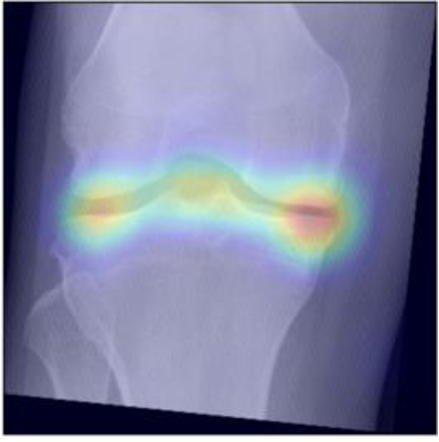

To gain insight into the basis of the CNN’s prediction, we used the GradCAM [24] approach and visualized the attention maps for the well-predicted knees. Examples of attention maps are presented in Figure 5. We observed that in various cases, the CNN paid attention to the compartment opposite to the one where degenerative change became visible during the follow-up visits. Additional examples of such attention maps are presented in Supplementary Figures 3, 4, 5 and 6.

Refer to caption

(a)

(b)

(c)

(d)

Figure 5: Examples of attention maps for progression cases and the corresponding visualization of progression derived using follow-up images from MOST datasets. Here, subplots (a) and (c) show the attention maps derived using a GradCAM approach. Subplots (b) and (d) show the joint-space areas from all the follow-up images (baseline to 84 months). Here, the subplot (b) corresponds to the attention map a) and the subplot (d) corresponds to the attention map (c).